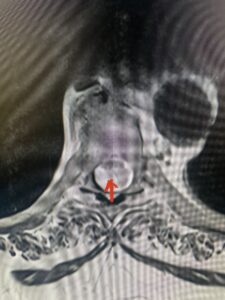

This 47-year-old male who four months prior was lifting weights developed sharp pain in his neck. After that he developed progressive numbness in his arms, neck pain and headache. He said that the right arm was worse than the left. On examination the patient had long tract weakness on the right side which included his triceps, finger extensors, hip flexors, and dorsiflexors. The patient did not have hyperreflexia. MRI (Fig. 2) demonstrated a massive, extruded disc herniation with severe cord compression. The patient because of progressive myelopathy and spinal cord compression was indicated for anterior cervical discectomy and fusion at C4-5 (Fig. 3). Patient had significant improvement of weakness and numbness post operatively.

Fig. 2a Sagittal T2-weighted cervical MRI demonstrating large C4-5 herniated disc with spinal cord compression (red arrow)

Fig: 2b Axial T2-weighted cervical MRI demonstrating spinal cord compression from C4-5 herniated disc (red arrow)